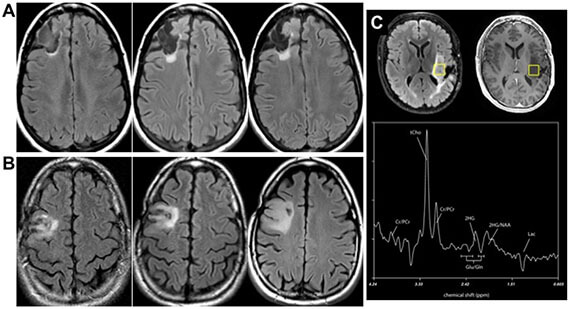

The Wilson laboratory is developing metabolism-targeted methods to identify tumors harboring IDHm, either (1) based on consumption of tumor-relevant metabolites or (2) direct detection of the IDHm enzyme via modification of known inhibitor structures. These tools will significantly impact the diagnosis and treatment of low-grade glioma and other lesions. These studies are performed in collaboration with the laboratory of Dr. Pavithra Viswanath and clinical collaborator Dr. Javier Villanueva-Meyer.